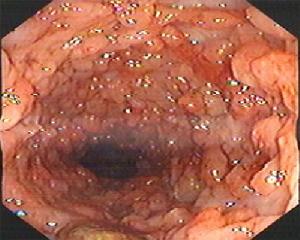

診斷上主要依靠纖維結腸鏡檢,因為約在90%~95%患者直腸和乙狀結腸受累,因此事實上通過纖維乙狀結腸鏡檢已能明確診斷。鏡檢中可看到充血、水腫的黏膜,脆而易出血。在進展性病例中可看到潰瘍,周圍有隆起的肉芽組織和水腫的黏膜,貌似息肉樣,或可稱為假息肉形成。在慢性進展性病例中直腸和乙狀結腸腔可明顯縮小,為明確病變範圍,還是套用纖維結腸鏡作全結腸檢查,同時作多處活組織檢查以便與克隆結腸炎鑑別。

慢性潰瘍性結腸炎 腸鏡表現2、黏膜活檢組織學檢查呈炎症性反應,同時可見糜爛、潰瘍、隱窩膿腫、腺體排列異常、杯狀細胞減少及上皮變化。